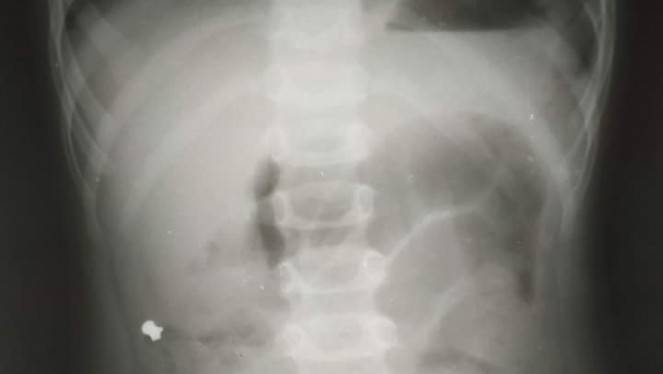

На дуже дивну знахідку натрапили львівські лікарі під час операції на апендиксі у 6-річного хлопчика і врятували йому життя. Про це ...

На Львівщині звичайні розваги для 10-річної дівчинки закінчилися болем в животі і операцією. Лікарі Обласної Дитячої Клінічної Лік...